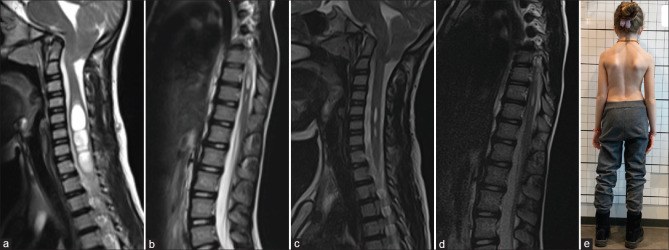

特发性脊柱侧凸(IS)通常与Chiari畸形(CM)和脊髓空洞相关,这些疾病被认为有一个共同的潜在原因:寰枢椎不稳定。寰枢稳定最近成为一种新的治疗选择。一名4岁女孩,表现为进行性脊柱侧凸(Cobb角28.6°)、颈部疼痛、CM和脊髓空洞。患者被诊断为寰枢中心或轴向不稳定,并接受C1-C2固定。术后,患者颈部疼痛明显缓解。随访显示进行性鼻窦缩小,x光显示Cobb角在18个月内下降至21°。本病例强调了寰枢椎稳定在IS合并CM和脊髓空洞的患者中阻止脊柱侧凸进展的潜力。与传统的多节段稳定不同,C1-C2固定提供了一种微创方法,并保留了生长年龄患者的脊柱活动能力。IS合并CM和脊髓空洞的病例应考虑寰枢椎不稳定。寰枢椎单独稳定可提供有效的治疗,并具有良好的临床和放射学结果。

Idiopathic scoliosis (IS) is frequently associated with Chiari malformation (CM) and syringomyelia, conditions thought to share a common underlying cause: Atlantoaxial instability. Atlantoaxial stabilization has recently emerged as a novel treatment option. A 4-year-old girl presented with progressive scoliosis (Cobb angle of 28.6°), neck pain, CM, and syringomyelia. The patient was diagnosed with central or axial atlantoaxial instability and underwent C1-C2 fixation. Postoperatively, she experienced significant relief from neck pain. Follow-ups demonstrated progressive syrinx reduction, while X-rays revealed a Cobb angle decrease to 21° in 18 months. This case highlights the potential of atlantoaxial stabilization to halt scoliosis progression in IS patients with CM and syringomyelia. Unlike traditional multisegmental stabilization, C1-C2 fixation offers a minimally invasive approach and preserves spinal mobility in growth-age patients. Atlantoaxial instability should be considered in IS cases with CM and syringomyelia. Atlantoaxial stabilization alone may provide effective treatment with favorable clinical and radiological outcomes.